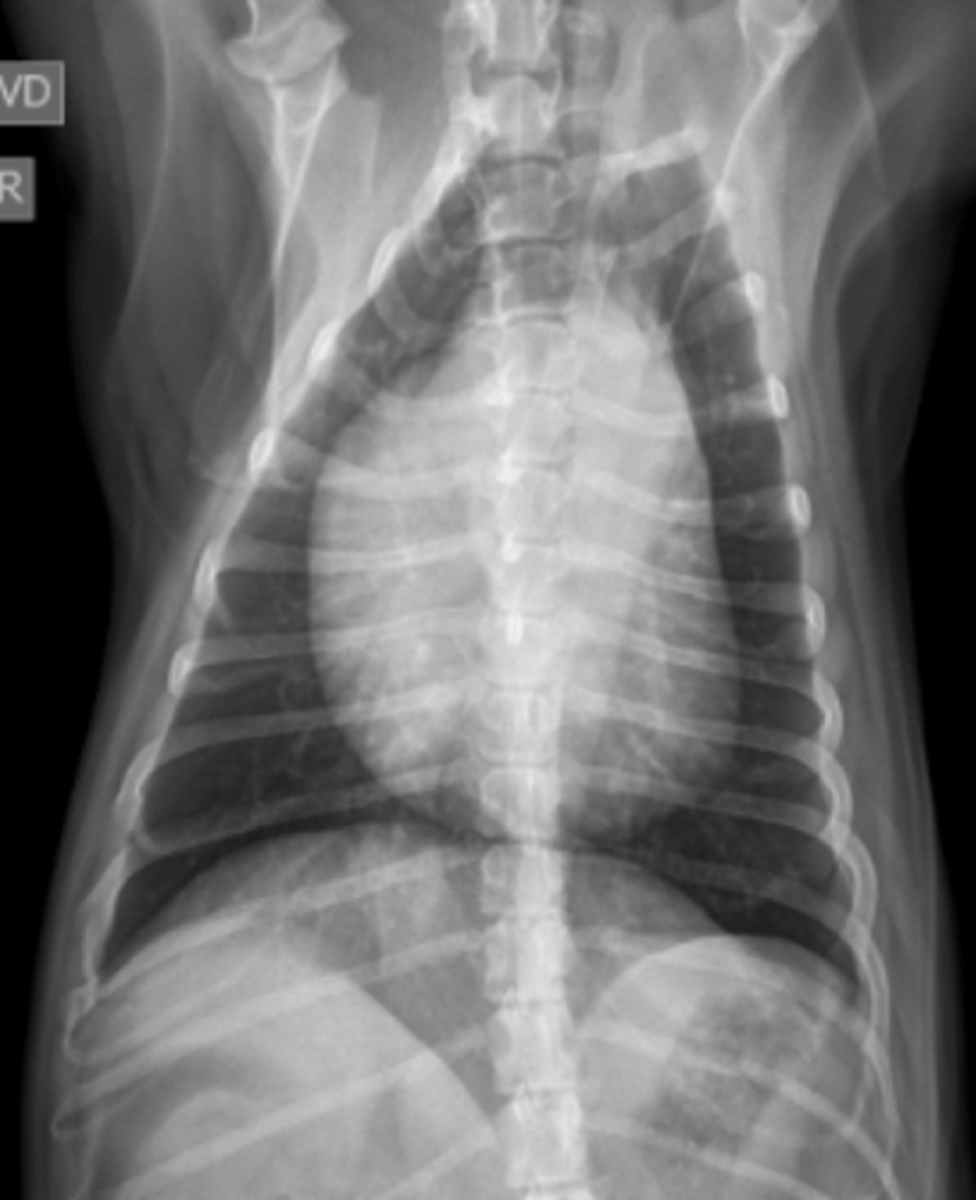

microcardias

(silueta separado de la diafragma)

patología:

(silueta separado del esternón)